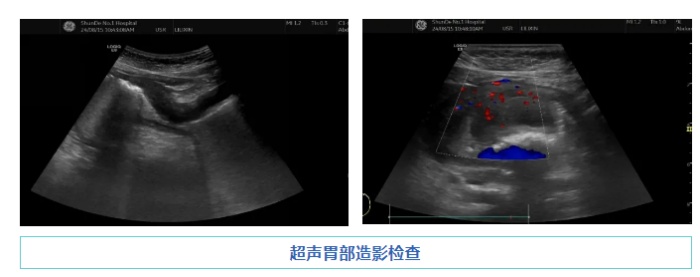

超聲胃部造影檢查發(fā)現(xiàn),李女士的胃壁廣泛增厚、隆起,報告提示胃癌可能,建議胃鏡活檢。后來李女士行胃鏡檢查,活檢病理結(jié)果顯示為胃印戒細胞癌。醫(yī)生檢查過程中的意外發(fā)現(xiàn),超聲胃部造影檢查的技術(shù)肯定,為患者“咯血”揭示了真相。同時,也為臨床醫(yī)生提供了新的診斷方向,為李女士后續(xù)的治療贏得了寶貴的時間。

超聲胃部造影,又稱胃腸充盈超聲檢查,是通過助顯劑充盈胃腔,消除胃腔內(nèi)氣體的干擾,達到顯示胃壁層次結(jié)構(gòu)及其病變、與毗鄰器官的關(guān)系;是檢查胃、十二指腸的又一項重要技術(shù)。